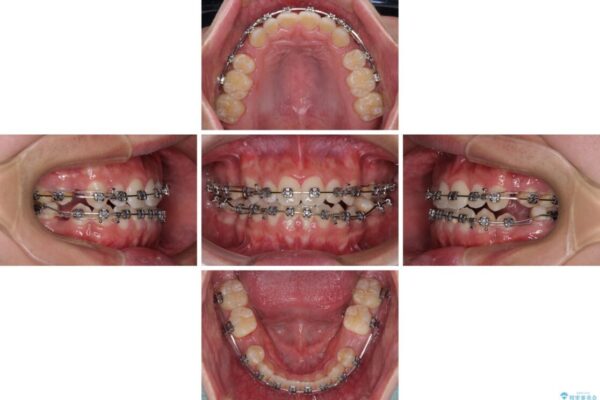

治療後

• 口元の突出感を改善 受け口傾向の咬み合わせの抜歯矯正 治療後画像